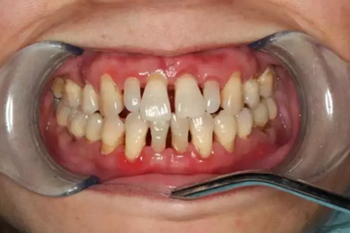

大多數(shù)情況都是來自外在的因素(如細菌)導致的出血,比如刷牙不到位導致牙菌斑、牙結(jié)石等附著在牙齒表面,長期刺激牙齒周圍的牙齦及牙周組織。

雖然起初沒有任何的不適癥狀,但是會使牙齦由健康慢慢變?yōu)檠装Y狀態(tài):充血紅腫、由堅韌的質(zhì)地慢慢變得很脆,一旦受到刷牙和咀嚼時的機械摩擦就極易出血。